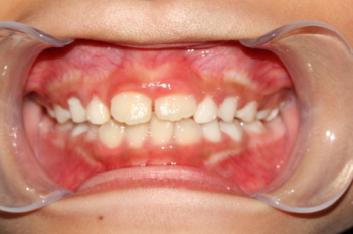

❸ 牙齿不齐:影响咬合关系,影响美观。

前

后